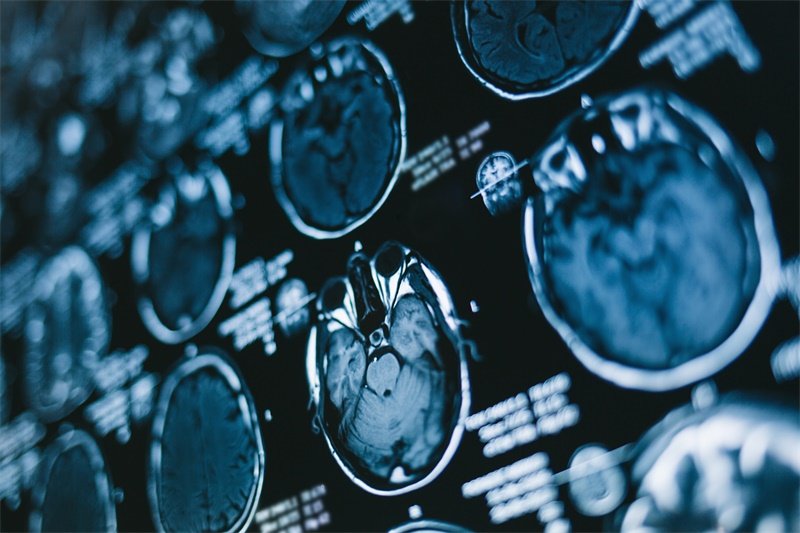

1. 影像学检查

影像学检查是诊断鞍区占位性病变的首要手段,包括CT和MRI。这些检查能清楚地显示鞍区的解剖结构及任何可能的病变,为后续治疗提供依据。